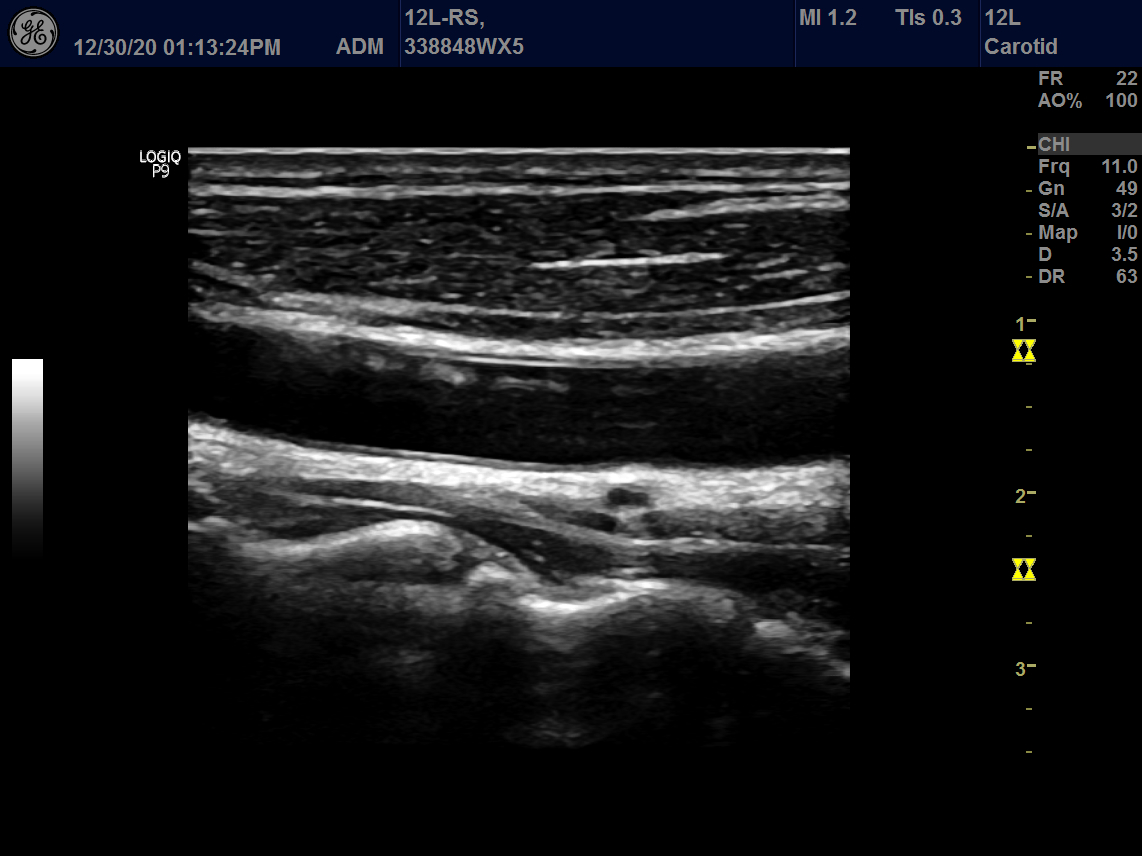

Intended use

Vascular, Small Parts and Musculoskeletal

GE 12L-RS Vascular Linear

Frequency Range: 13 – 4 MHz

GE 12L-RS Vascular Linear for Vascular, Small Parts and Musculoskeletal